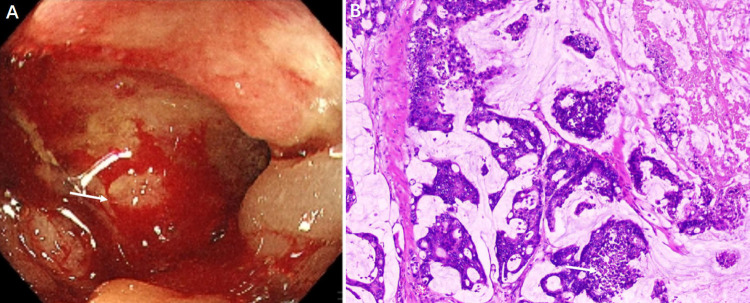

Clostridioides difficile infection (CDI) is a major healthcare-associated concern, particularly in the elderly. While CDI typically manifests as toxin-mediated colitis, hematogenous dissemination leading to bacteremia is relatively rare and associated with high mortality. We report an unusual case of C. difficile bacteremia in an octogenarian female patient occurring shortly after right hemicolectomy for ascending colon adenocarcinoma. This critically ill patient presented with bloodstream infection in the ICU following surgery. Multiple risk factors converged, including advanced age, extensive colorectal surgery with mucosal disruption, malignancy, and broad-spectrum antibiotic exposure. Blood culture identification required specific anaerobic processing. Combined intravenous and high-dose oral vancomycin therapy, guided by rapid microbiological confirmation, led to successful resolution of the bacteremia. This case underscores the potential for life-threatening C. difficile bacteremia in vulnerable elderly patients post-colorectal cancer surgery, highlights the diagnostic challenges (necessitating anaerobic blood cultures), and emphasizes the critical importance of early suspicion, aggressive multimodal therapy, and meticulous antimicrobial stewardship in this high-risk population. It serves as a crucial reminder of this devastating complication.